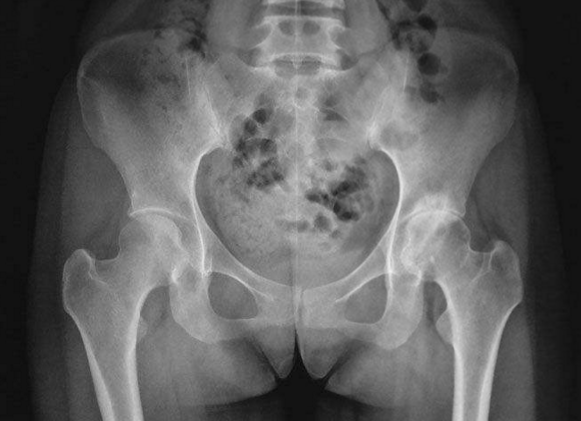

Nửa tiếng sau, Phi Phi đã nằm trên giường bệnh, bác sĩ tiêm một ít thuốc giảm đau cho cô để giảm đau tạm thời, sau khi kiểm tra, Phi Phi bị loãng xương, xương rất dễ gãy, khiến hông cô bị đau do xương bị lệch.

Bác sĩ nói với Phi Phi rằng mật độ xương của cô ấy rất thấp và xương của cô ấy trông giống như "tổ ong", nhưng điều này khiến cô đầy nghi ngờ, cô ấy mới 28 tuổi, làm sao xương có thể trở nên như thế này?